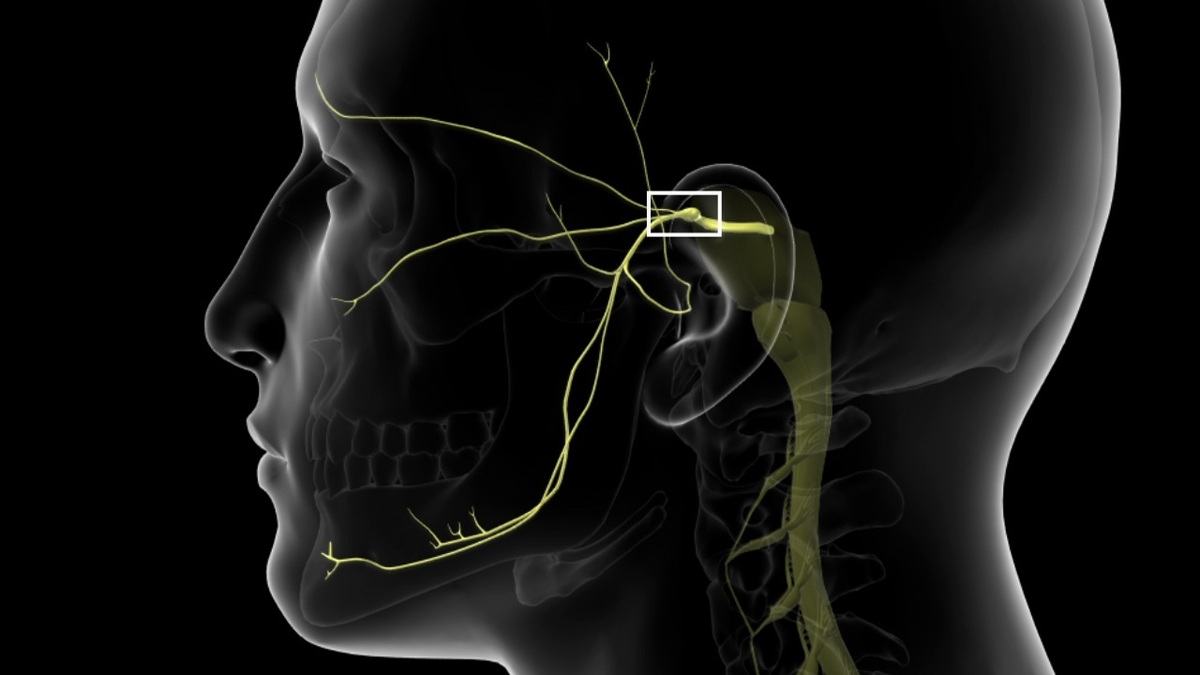

قیمت: 45٬000 تومان - دسته بندی فایل: علوم پزشکیپاورپوینت بررسی تومور شوانوما

خرید پاورپوینت حرفه ای با موضوع بررسی تومور شوانوما از لوکس فایل